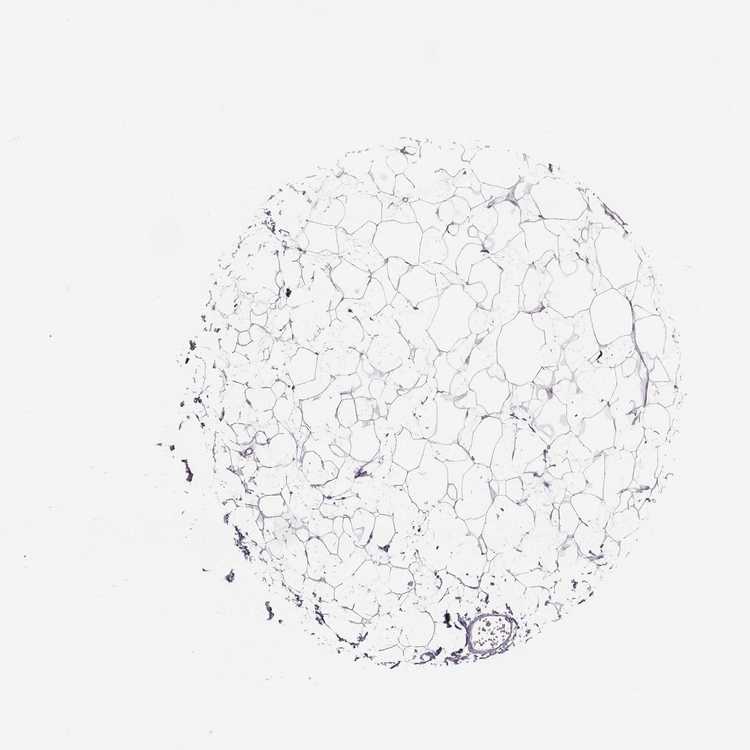

BREAST - Antibody stainingi

Antibody staining in the annotated cell types in the current human tissue is reported as not detected, low, medium, or high, based on conventional immunohistochemistry profiling in selected tissues. This score is based on the combination of the staining intensity and fraction of stained cells.

Each image is clickable and will lead to virtual microscopy that enables deeper exploration of all samples and also displays staining intensity scores, fraction scores and subcellular localization as well as patient and tissue information for each sample.

Antibody HPA052446

Adipocytes Not detected

Glandular cells Not detected

Myoepithelial cells Not detected